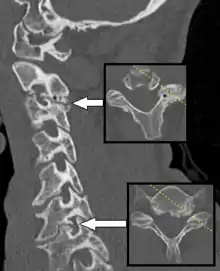

دَاء الفَقَار أو تَنَكُّس الفَقار هو انتكاس العمود الفقري لأي سبب. بالمعنى الدقيق، يشير إلى هشاشة العظام في العمود الفقري، وهو تآكل وتمزق العمود الفقري المرتبط بتقدم العمر، وهو السبب الأكثر شيوعًا للإصابة بداء الفقار. تؤثر العملية التنكسية في هشاشة العظام بشكل رئيسي على الأجسام الفقرية، والثقب العصبي، ومفاصل الوجه ( متلازمة الوجه ). إذا كانت شديدة، فقد تسبب ضغطًا على النخاع الشوكي أو جذور الأعصاب مع اضطرابات حسية أو حركية لاحقة، مثل الألم والتنمل وعدم التوازن وضعف العضلات في الأطراف. عندما تقل المسافة بين فقرتين متجاورتين، قد يؤدي ضغط جذر العصب الخارج من الحبل الشوكي إلى اعتلال الجذور (اضطرابات حسية وحركية، مثل ألم شديد في الرقبة أو الكتف أو الذراع أو الظهر أو الساق، مصحوبًا بضعف العضلات ). أقل شيوعًا، قد يؤدي الضغط المباشر على النخاع الشوكي (عادةً في العمود الفقري العنقي) إلى اعتلال النخاع، الذي يتميز بضعف عالمي، وخلل في المشي، وفقدان التوازن، وفقدان السيطرة على الأمعاء أو المثانة. قد يعاني المريض من صدمات (تنمل) في اليدين والرجلين بسبب انضغاط العصب وقلة تدفق الدم. في حالة إصابة فقرات العنق، يتم تسميتها بداء الفقار الرقبية. يسمى داء الفقار أسفل الظهر داء الفقار القطني. المصطلح مشتق من اليونانية القديمة σπόνδυλος spóndylos، "فقرة"، في الجمع "فقرات - العمود الفقري".

التشخيص

- تعد فحوصات التصوير بالرنين المغناطيسي والتصوير المقطعي المحوسب مفيدة في تشخيص الألم ولكنها ليست نهائية بشكل عام ويجب أخذها في الاعتبار مع الفحوصات البدنية والتاريخ.